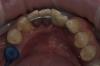

Art 7 Опубликовано 30 марта, 2013 Поделиться Опубликовано 30 марта, 2013 фото до фото после модельпациент хочет закрыть дефект при помощи имплантации,но чуть позжени чего временного не хотел,кое как уговорил на эту конструкцию чтобы сохранить место 1 Ссылка на комментарий

GurDoc Опубликовано 7 апреля, 2013 Поделиться Опубликовано 7 апреля, 2013 (изменено) фото до фото после модельпациент хочет закрыть дефект при помощи имплантации,но чуть позжени чего временного не хотел,кое как уговорил на эту конструкцию чтобы сохранить местоОригинально!)Подскажите облицовка пластмассовая?На что фиксировали?"ни чего временного не хотел,кое как уговорил на эту конструкцию чтобы сохранить место"-а на какую времянку он не соглашался?п.с."елочка " впереди -грамотно))) Изменено 7 апреля, 2013 пользователем GurDoc Ссылка на комментарий

Art 7 Опубликовано 7 апреля, 2013 Автор Поделиться Опубликовано 7 апреля, 2013 Оригинально!)Подскажите облицовка пластмассовая?На что фиксировали?"ни чего временного не хотел,кое как уговорил на эту конструкцию чтобы сохранить место"-а на какую времянку он не соглашался?п.с."елочка " впереди -грамотно)))Пластмасса да, на Фуджи 1Ему вообще ни чего не хотелось)Ёлочка=скученность??? Ссылка на комментарий